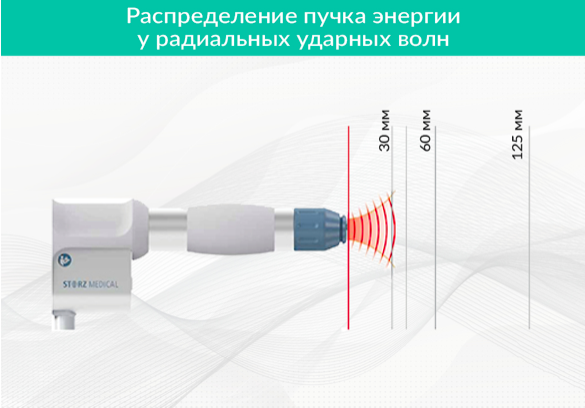

Наряду с «классическими» ударными волнами, о которых идет речь выше, выделяют еще радиальные ударные волны. В акустике они имеют отношение к так называемым расфокусированным волнам давления, которые расходятся из источника широким потоком во все стороны и чем-то напоминают воду, льющуюся из душа. Радиальные ударные волны не имеют фокусного пятна, где концентрируется энергия. Их начали использовать в медицине в 1999 г.

Характеристики радиальной волны давления сильно отличаются от «классических» ударных волн, в том числе и по эффектам, оказываемым на организм. Для них характерен:

- растянутый во времени пологий фронт — давление в области повышенного давления нарастает в миллисекундном диапазоне (то есть более длительно, чем у «классических» ударных волн);

- небольшие, относительно «классической» ударной волны, величины давления перед и за фронтом, и, соответственно, высокие потери энергии в первых 5 мм тканей тела при вхождении;

- равномерное распределение во все стороны от источника ударной волны;

- малая плотность потока энергии на единицу площади — в десятки раз меньшая, чем у фокусированной волны (Рисунок 4).

Терапевтические эффекты ограничены только высокой стимуляцией «тканевых эффектов» — уменьшение воспаления, прорастание капилляров, приток стволовых клеток и т.д. в первых 2-х сантиметрах ткани тела.

Радиальная волна не проникает глубоко в тело и не вызывает эффект разрыхления тканей – в этом ее большой недостаток. Но зато особенно успешным оказалось лечение заболеваний с широко распространенными и неглубоко расположенными внутри тканей проблемами – ожогов и язв, диабетической стопы, целлюлита, сосудистой недостаточности, пяточной шпоры и эпикондилита.

Рисунок 4. Радиальная ударная волна